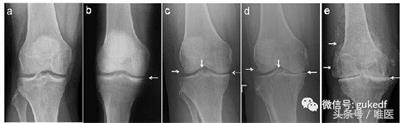

8. 对于关节内软骨剥脱形成游离体,以及半月板撕裂产生卡压、交锁症状的患者可以考虑膝关节镜下清理游离体(图4)和增生的滑膜策划,或镜下微创缝合损伤撕裂的半月板(图5)。前(后)交叉韧带断裂的可行关节镜下的韧带重建手术(图6)。

图4. 膝关节镜清理游离体